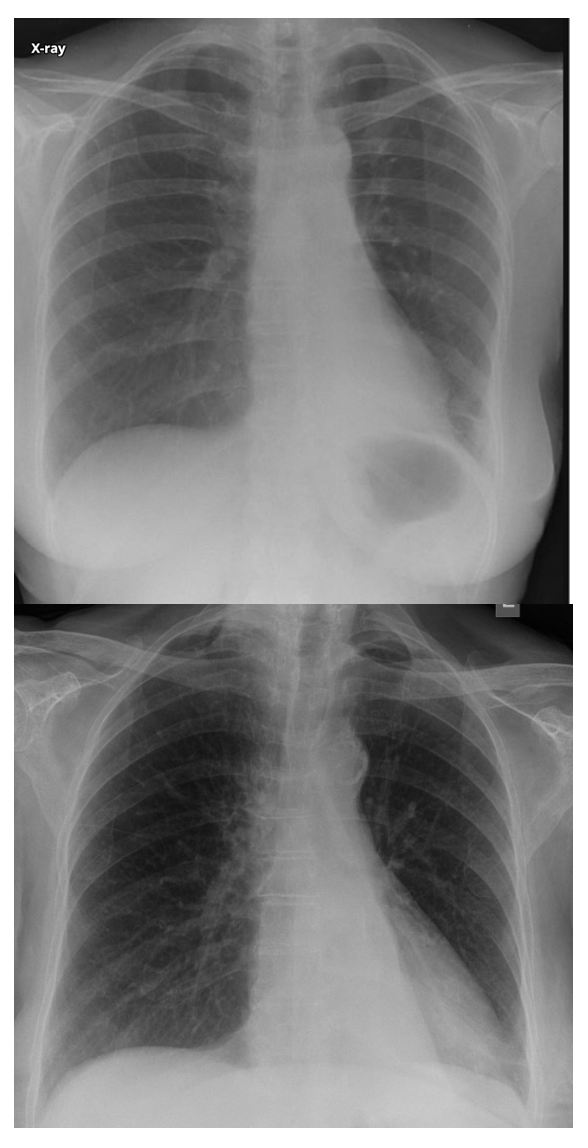

What are the features of RML collapse on CXR?

CXR features: (7)

R mid to lower air space consolidation – can be subtle in PA, so lateral CXR can help

Horizontal fissure no longer visible

Obscured R heart border

Elevated R. hemidiaphragm

Crowding of R sided ribs

Mediastinum shifted to the right

Displaced R hilum

Lateral CXR:

Triangular opacity projecting over cardiac shadow

Horizontal fissure not visible